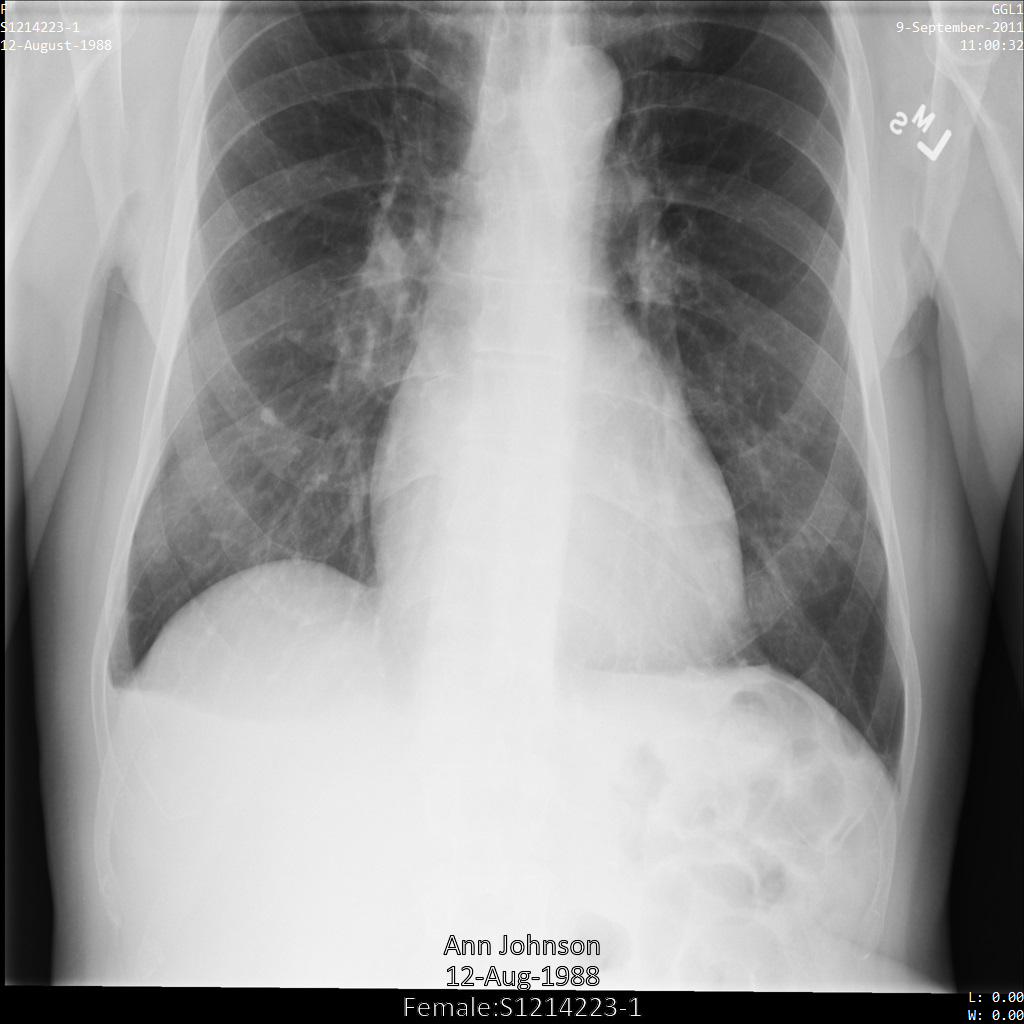

A imagem seguinte mostra uma radiografia não ocultada de um paciente:

Depois de enviar a imagem para a Cloud Healthcare API através da opção REDACT_SENSITIVE_TEXT, a imagem é apresentada da seguinte forma:

Pode ver que ocorreu o seguinte:

- O

PERSON_NAMEna parte inferior esquerda da imagem foi ocultado - O

DATEna parte inferior esquerda da imagem foi ocultado

O sexo do paciente não foi ocultado porque não é considerado texto sensível de acordo com os infoTypes DICOM predefinidos.